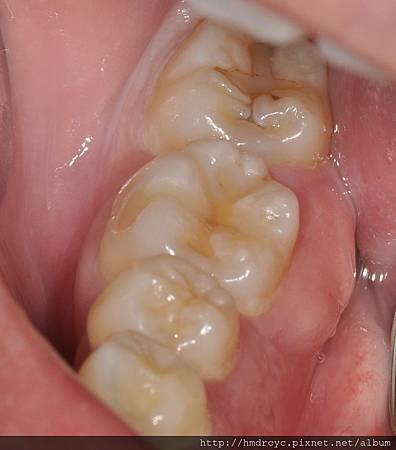

[牙肉腫很大 痛是還好 只是有點擔心]

這種牙肉發炎後腫起來

是因為發炎的部位積膿

在牙齒與牙肉中間排不出來

最後過多的膿把牙肉都撐開變成膿包

病友們通常不會感覺過度疼痛

但不理它後越腫越大